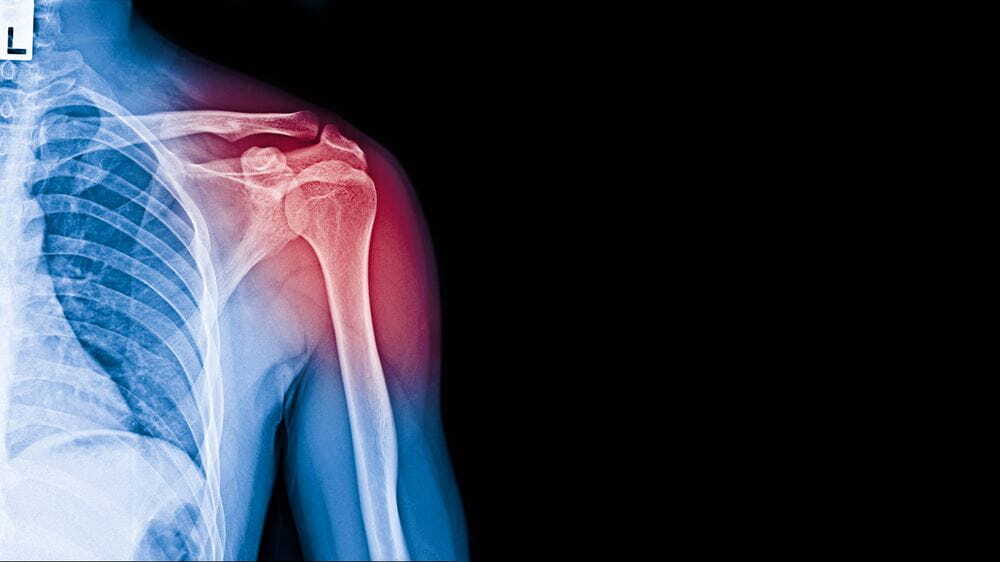

어깨뼈 골절로 인한 도수치료 비용은 일반적으로 실비보험으로 청구 가능합니다. 그러나 교통사고로 인한 어깨 골절의 경우, 도수치료 비용은 자동차 보험으로 처리되지 않는 경우가 많습니다. 소송을 통해 보상을 받는 경우도 있겠지만, 실질적으로 도수치료에 대한 보상을 받기 어려울 수 있습니다. 따라서 실비보험을 가입하고 있는 경우에는 실비보험을 통해 어깨뼈 골절로 인한 도수치료 비용을 청구하는 것이 유용할 수 있습니다.

어깨뼈 골절로 인한 입원 기간, 수술 후 물리치료 및 도수치료 비용, 그리고 실비보험 적용 여부는 개별 환자의 상황에 따라 다를 수 있습니다. 어깨뼈 골절을 치료할 때는 의사의 지시를 따르고, 물리치료와 재활치료를 꾸준히 받아야 합니다. 도수치료 비용은 실비보험을 통해 청구할 수 있으므로 보험 가입 여부를 확인하고 필요한 보험 절차를 따르는 것이 중요합니다.